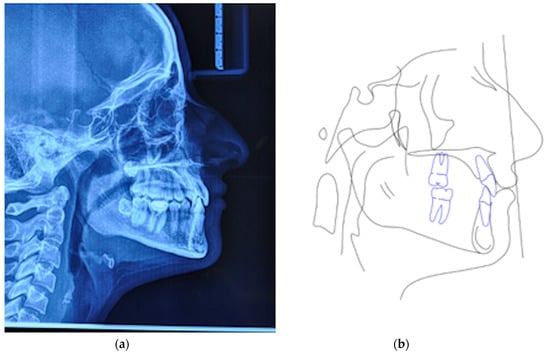

A 25 years old female attended consultation for orthodontic treatment to enhance the aesthetic of the smile. In particular, the chief complain was the crowded teeth along with the presence of wide buccal corridors while smiling. Facial analysis revealed retrognatic profile with labial competence, no gingival exposure during smiling along with extensive buccal corridors (Figure 7a–c). Intra-oral examination revealed class I molar and canine relationships, significant maxillary and mandibular crowding, mild maxillary transversal deficiency with cross-bite on the right side due to mandibular shift toward cross-bite side, significant anterior overbite (Figure 8a–e). Panoramic examination showed healthy condition of the upper first molars that would support the dental anchorage of the MSE device (Figure 9). Cephalometric analysis (Figure 10a,b) confirmed that the patient presented skeletal class I maxillo-mandibular relationship with retruded profile, mesiofacial growth pattern and anterior overbite. Patient approved the usage of photographic and radiographic records for the purpose of publication, by signing a specific form.

Figure 8.

Intra-oral patient’s examination. (a) Right lateral occlusion, (b) front view, (c) left lateral occlusion, (d) occlusal view of the maxillary arch, (e) occlusal view of the mandibular arch.

Figure 10.

(a) Lateral cephalogram, (b) pre-treatment cephalometric tracing.